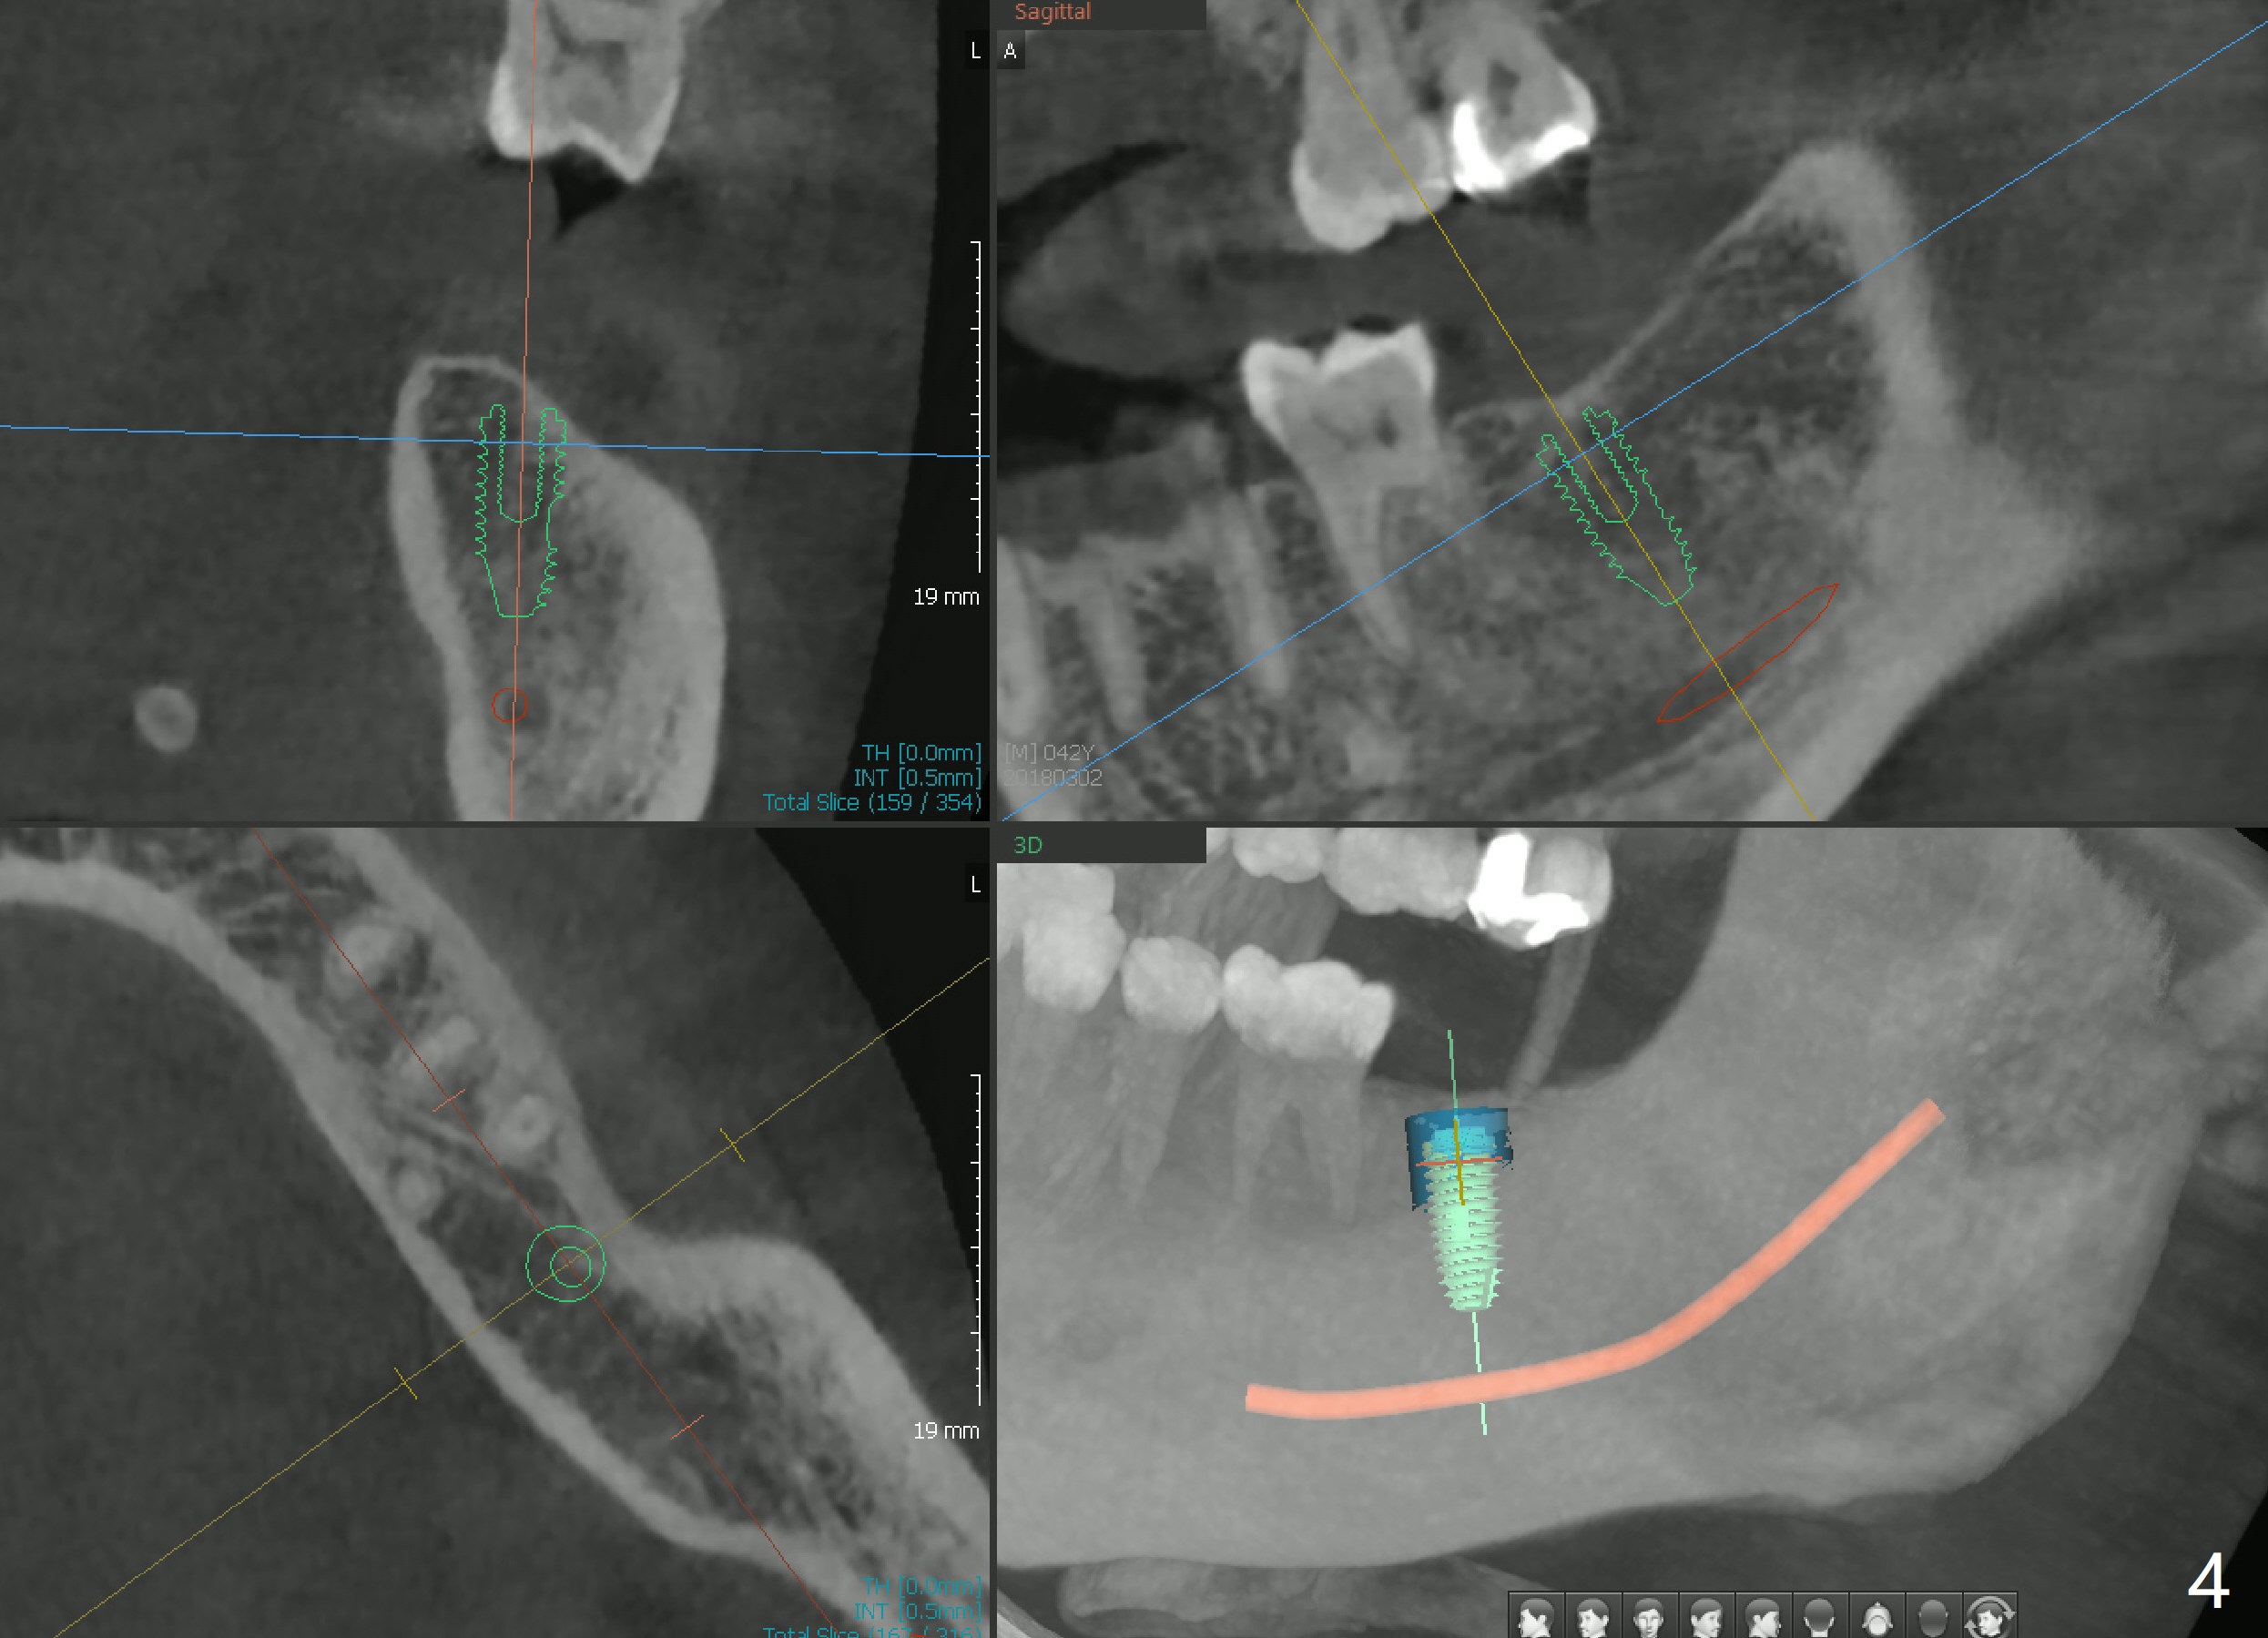

A 42-year-old man has lost #18 (due to 3rd molar impaction) for ~ 5 years (Fig.1). Because of the indistinct Inferior Alveolar Canal (Fig.3 ? vs. Fig.2 red dashed line), CBCT is taken for guided surgery (Fig.4: 5x11.5 mm).